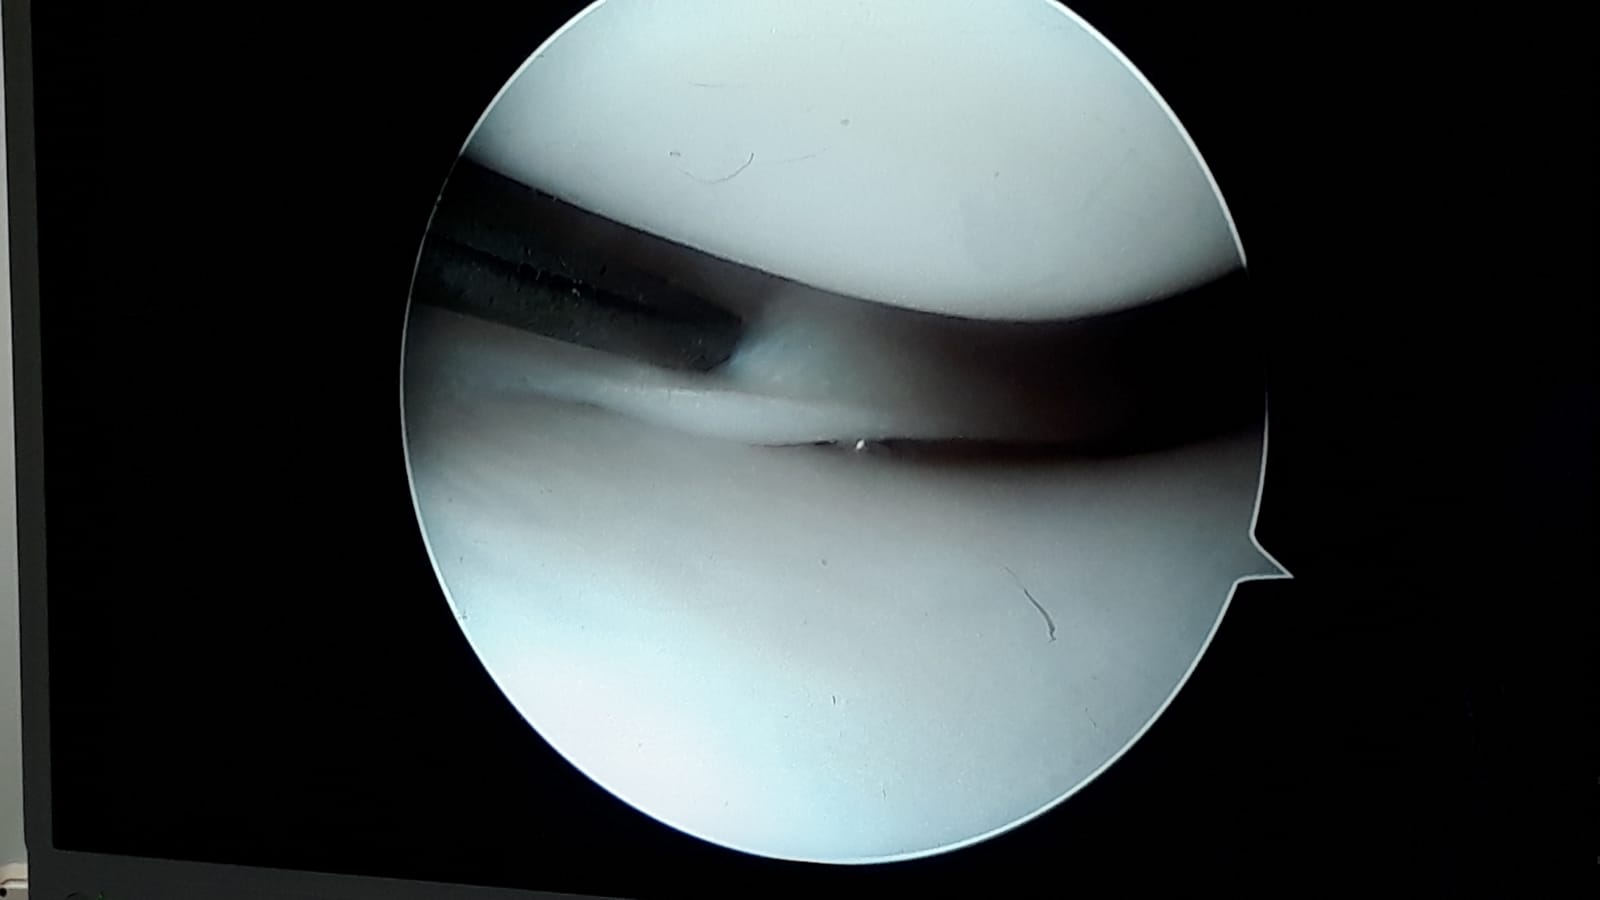

Lesioni osteoarticolari

Le lesioni osteoarticolari derivano da traumi quali lussazioni, fratture, distorsioni, contusioni o tendiniti che a loro volta causano l'usura delle cartilagini o il deterioramento dei tendini ; le più comuni riguardano il gomito, il polso, l'anca, la spalla, il ginocchio e la caviglia specialmente se il soggetto colpito pratica attività sportiva.